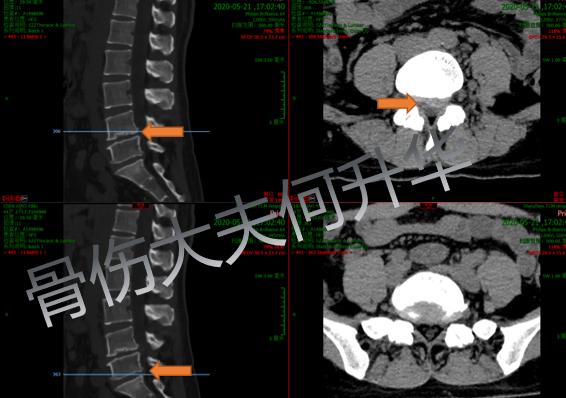

入院后CT横断面提示腰4/5左侧

椎间盘突出,腰4椎体终板炎表现